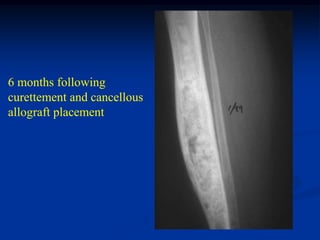

6 months following

curettement and cancellous

allograft placement